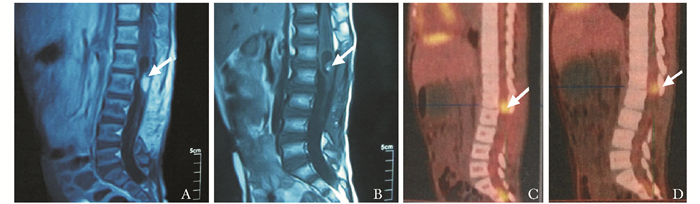

结果  5岁男孩临床主要表现为臀部疼痛进行性加重, 性早熟, 血清及脑脊液甲胎蛋白、β-人绒毛膜促性腺激素明显升高, 磁共振成像示L2-3水平椎管内占位, 组织病理示椎管内混合性生殖细胞瘤(生殖细胞瘤+畸胎瘤)。采用18F-脱氧葡萄糖正电子发射计算机断层显像可协助显示病灶, 并通过监测最大标准摄取值的变化评估疗效及监测病情有无复发。该患儿放疗效果差, 化疗效果尚好。

Results  The clinical manifestations of the 5-year-old boy included the progression of hip pain and precocious puberty. Alpha-fetoprotein(AFP) and β-human chorionic gonadotrophin (β-HCG) levels elevated obviously in serum and cerebrospinal fluid. Magnetic resonance imaging (MRI) demonstrated an intraspinal mass extending from L2 to L3. Histopathological examination showed mixed germinoma (germinoma and teratoma). 18F-fluorodeoxy-glucose positron emission tomography(18F-FDG-PET) was applied to help displaying the lesion, evaluating therapeutic effect and monitoring recurrence via the maximum standardized uptake value(SUVmax). The child responded poor to radiotherapy, while fair to chemotherapy.